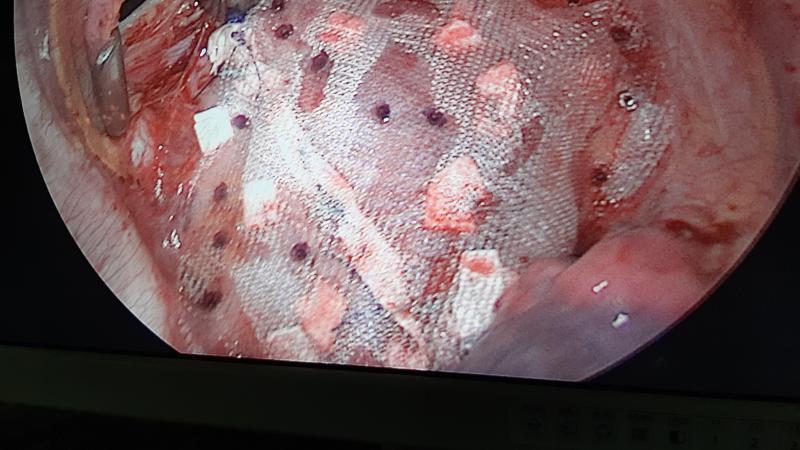

BEST CARDIAC SURGERY – VATS [THORACOSCOPY] & GENERAL THORACIC SURGERY

CARDIO THORACIC AND VASCULAR SURGERY